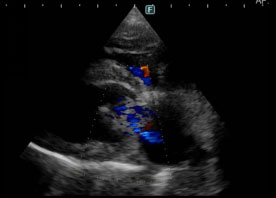

次に雑音の原因や心臓の機能を確認するため、心臓の超音波検査を実施しました。

左心房と左心室の間にある僧帽弁から、重度に逆流所見が確認できました。(図2参照)

ワンちゃんで多い僧帽弁閉鎖不全症(弁膜症)であることがわかりました。

図2